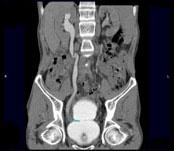

问题 男,53岁,无痛性血尿2个月余,CT扫描如图示,下列说法正确的是 ( )

选项 A、考虑为输尿管移行细胞癌 B、考虑为输尿管内血块 C、软组织肿块边缘毛糙不平 D、其上方的输尿管扩张 E、右侧输尿管下段可见沿输尿管走行的软组织肿块影

答案 ACDE